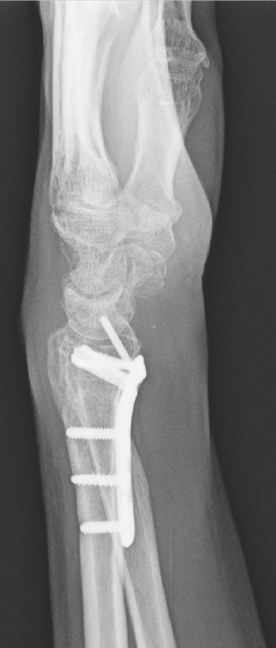

X-rays will be used to confirm the diagnosis. Fortunately, many of these fractures can be treated without surgery. Sometimes, the best thing is to push the fracture back into a better position and then hold it there with a cast. However, there are occasions where surgery is the best option. Surgery allows for the bones to be held in a better position more securely. With surgery, the bones can be held in place with pins, plates, and screws, and sometimes a combination of all of these. No matter the treatment, these fractures usually require at least 6 weeks to heal before it is ok to begin using the hand and wrist without restriction, but it often takes months before the pain and the stiffness fully resolve.

60-year-old female without other medical problems fell and landed primarily on her left hand and wrist. She had immediate pain and deformity at the wrist. She went to the emergency room where x-rays were performed showing her injury – a distal radius fracture. An attempt was made at improving the fracture position by the emergency room doctors and she was splinted. She was then referred to my clinic. She was seen soon afterwards. It was noted on new x-rays that the broken bone was in a less than ideal position. After a thorough discussion of the patient’s goals and concerns, surgery was felt to be the best option for her. Surgery was performed one week after her initial injury under general anesthesia. She was allowed to begin moving her wrist after her first post-operative visit 10 days after surgery and begin full weight bearing on the hand and wrist just under 6 weeks after surgery. She now has full function.